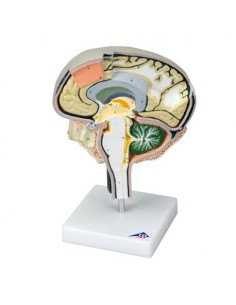

Scopri il Mondo dell’Anatomia con Modelli anatomici di Precisione

Modelli Anatomici Dettagliati per Ogni Necessità

Dal cranio in 22 parti con incastri magnetici ai modelli di colonna vertebrale, da quelli di articolazioni a quelli di cuore, ogni pezzo della nostra collezione è progettato per un’immersione totale nello studio dell’anatomia umana. I nostri modelli, realizzati tramite scansioni di ossa vere, garantiscono un’esperienza tattile autentica e una fedeltà di peso quasi identica agli originali.

Strumenti Didattici Innovativi per l’Educazione e la Pratica Medica

Essenziali per studenti e professionisti, i nostri modelli anatomici sono strumenti didattici che permettono di osservare le strutture anatomiche con precisione, eliminando la necessità di dissezioni o studi invasivi. Sono inoltre utili per spiegare ai pazienti le patologie, rendendo la comunicazione più efficace e risparmiando tempo prezioso.